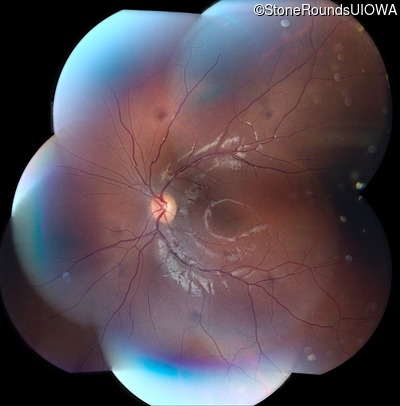

AR Stargardt Disease (IIA)

AR Stargardt Disease (IIA)

This 11 year old female first had difficulty seeing the blackboard at age 8. Later, she developed some photophobia.